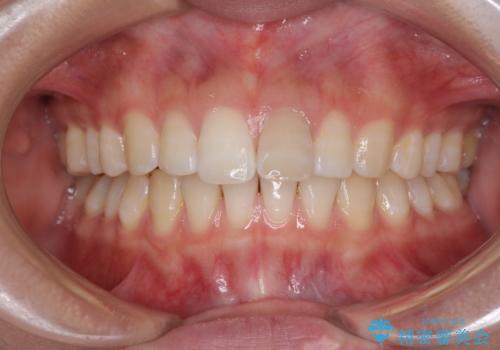

- 変色した前歯と突出した口元を気にして来院された患者様です。

口元の突出感はインビザラインにより歯列を整え、その後に、前歯をオーダーメイドタイプのオールセラミッククラウンにて補綴治療することとしました。

長時間のマウスピース装着と、患者様自身でのゴムかけに協力いただき、口元の突出感をしっかりと改善することができました。

前歯のオールセラミッククラウンもまるで本物の歯のように仕上がり、患者様には大変満足していただきました。